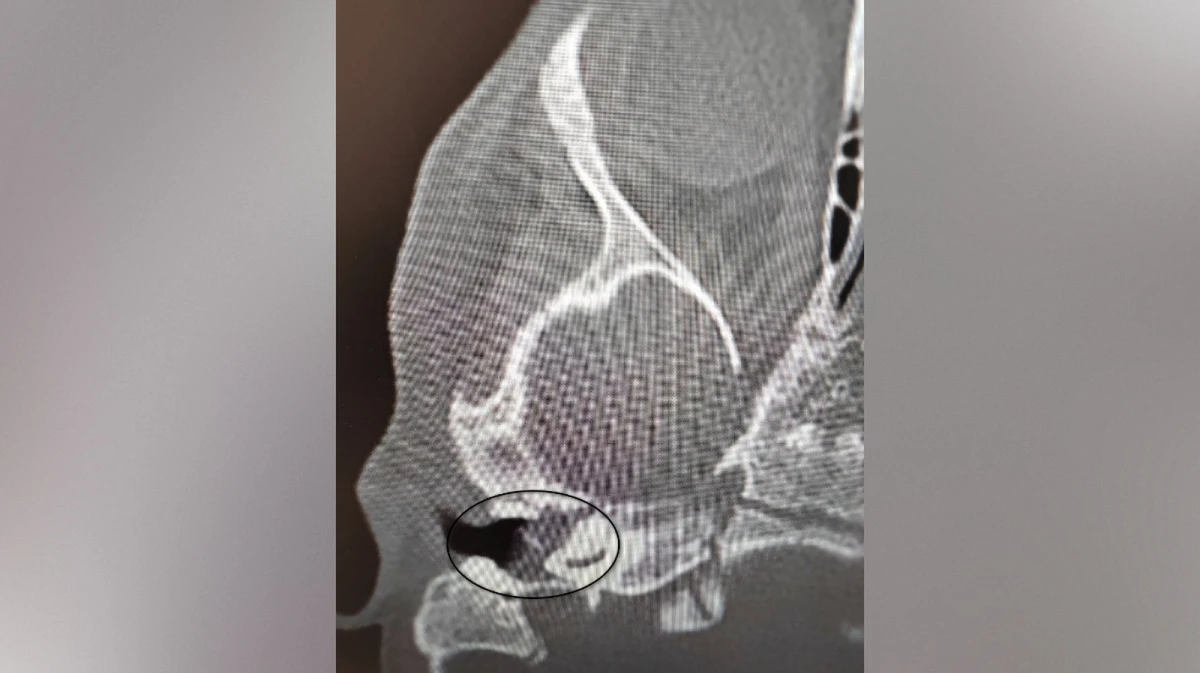

Врачи Воронежской областной детской клинической больницы №1 (ВОДКБ №1) вылечили редкое заболевание у двухлетней пациентки и смогли сохранить ее слух. У ребенка был правосторонний хронический гнойный средний отит и подозрение на врожденную холестеатому барабанной полости (кистозное патологическое образование в среднем ухе. – Прим. ред.). Это заболевание встречается особенно редко в таком раннем возрасте. Из-за холестеатомы девочка могла потерять слух. Об этом сообщили в пресс-службе министерства здравоохранения Воронежской области в среду, 5 ноября.

После ОРВИ у ребенка появилась боль в ухе. Консервативное лечение не принесло результатов, ситуация осложнилась парезом лицевого нерва – слабостью мимических мышц. Врачи приняли решение о хирургическом лечении. Заведующий оториноларингологическим хирургическим отделением Антон Мащенко провел сложную операцию, под контролем операционного микроскопа он удалил холестеатому, провел декомпрессию лицевого нерва и восстановил механизм звукопроведения.

Своевременное хирургическое вмешательство позволило не только устранить опасное образование и восстановить функцию нерва, но и сохранить слух ребенка. Послеоперационный период прошел без осложнений, парез лицевого нерва удалось купировать. На пятый день после операции девочку выписали домой.